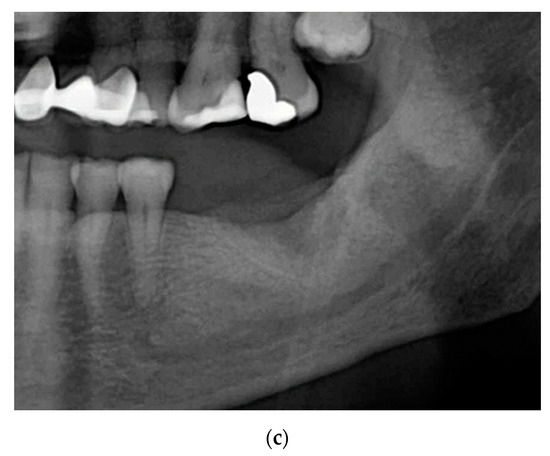

2.1. Case 1: Conservative Treatment

2.2. Case 2: Conservative Treatment Plus Surgery

2.3. Case 3: Conservative Treatment + SURGERY + PRF-L